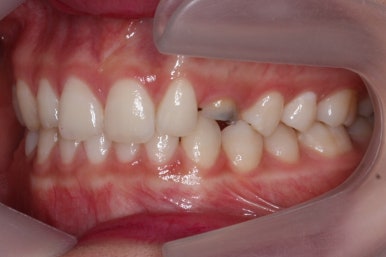

위 사진들은 부산매복치아교정 키다리아저씨치과에 처음 내원하셨을 때의 모습입니다.

화살표 표시한 부분이 바로 영구치 송곳니가 있어야 할 자리인데, 매복이 되어있고 대신 유치가 여전히 남아있는 모습입니다.

환자분의 나이가 만으로 15세였는데, 치과에 처음 올 때 해당 치아가 영구치가 그냥 썩은 줄 알고 오시는 경우가 많습니다.

이번 환자분의 경우는 아랫니는 약간 삐뚤함이 있지만 굳이 교정치료를 원하지 않으셨기 때문에 윗니들만 부분교정으로 해결하기로 했습니다.

이상적으로라면 위-아래를 한 쌍으로 해야 교합을 맞추기에 유리하지만 이번의 경우는 윗니만 해도 충분히 교합을 맞출 수 있겠다고 판단하여 부분교정을 하였습니다.